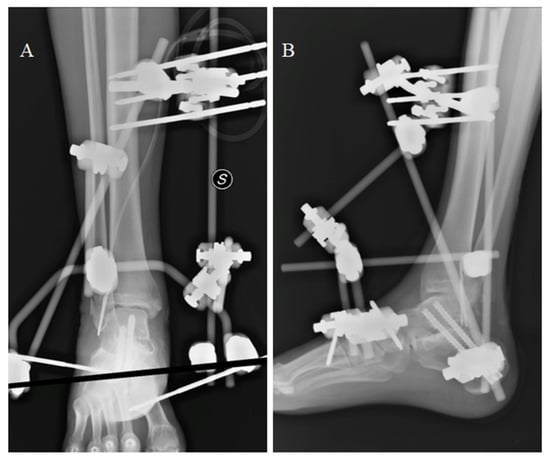

Post-operative recovery was uneventful. After two months, the patient started to complain of ankle pain and swelling: Single-photon emission computed tomography (SPECT-CT) confirmed the clinical suspicion of a deep tissue infection involving the reimplanted talus (Figure 3). The talus was removed and replaced by a new spacer in antibiotic-coated cement. A negative pressure treatment was applied to facilitate soft tissue healing.

Figure 3.

SPECT CT suggesting a deep tissue infection of the reimplanted talus. Red hyphens point out the site of infection.